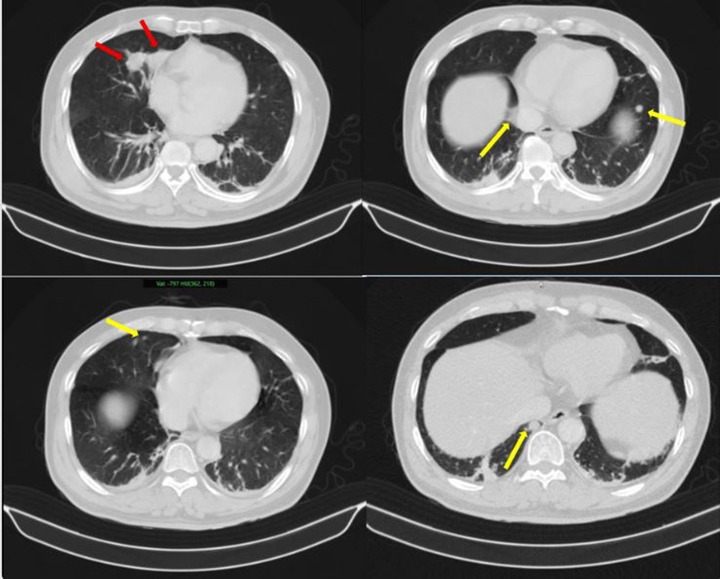

Thông tin từ Bệnh viện Bạch Mai, nam bệnh nhân nhập viện trong tình trạng tiểu khó kéo dài. Qua thăm khám và thực hiện các kỹ thuật cận lâm sàng như chụp cắt lớp vi tính, cộng hưởng từ, xạ hình xương và đặc biệt là PET/CT, các bác sĩ phát hiện tổn thương tại tuyến tiền liệt cùng nhiều khối u ở phổi, tuyến thượng thận và xương.

Thách thức lớn nhất trong trường hợp này là xác định bản chất các tổn thương: đâu là khối u nguyên phát, đâu là di căn. Nếu chẩn đoán không chính xác, việc lựa chọn phương pháp điều trị có thể sai lệch, ảnh hưởng trực tiếp đến hiệu quả điều trị.

Kết quả sinh thiết và phân tích mô bệnh học kết hợp hóa mô miễn dịch giúp làm rõ: khối u phổi là ung thư biểu mô tuyến của phổi, trong khi khối u tuyến tiền liệt là ung thư biểu mô tuyến với điểm Gleason 9 - thuộc nhóm nguy cơ cao. Hai loại ung thư này có nguồn gốc hoàn toàn khác nhau, không phải di căn chéo.